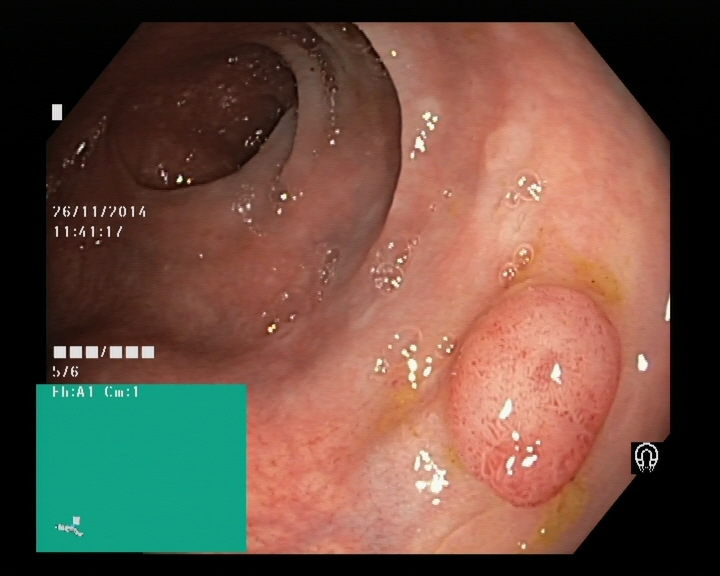

The Kvaris-SEG (Jha et al., 2020c) training dataset can be downloaded from https://datasets.simula.no/kvasir-seg/. It contains 1,000 polyp images and their corresponding ground truth mask as shown in Figure 1. The dataset was collected from real routine clinical examinations at Bærum Hospital in Norway by expert gastroenterologists. The resolution of images varies from to pixels. Some of the images contain a green thumbnail in the lower-left corner of the images showing the scope position marking from the ScopeGuide (Olympus) (see Figure 2). We annotate another separate dataset consisting of 160 new polyp images and use the resulting dataset as the test set to benchmark the participants’ approaches. Figure 2 shows some examples of test images used in the challenge.